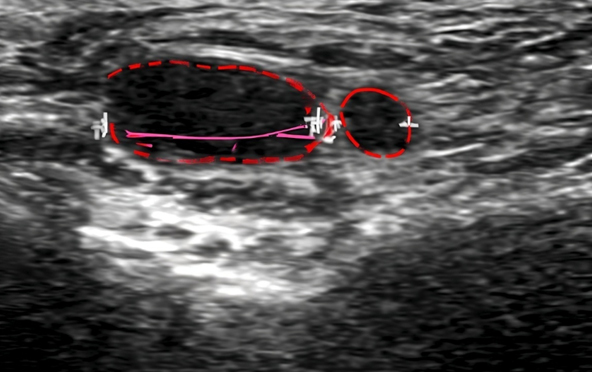

히알라제(테르가제)는 히알루론산(HA)을 분해하는 효소로, 히알루론산 필러를 녹이는 데 사용됩니다. 초음파로 필러의 정확한 위치·층·분포를 확인한 뒤, 초음파를 보면서 목표 부위에 맞춰 주입하면 ‘필러가 없는 곳에 주사해 효과가 떨어지는 상황’을 줄이고 보다 정밀한 교정을 기대할 수 있습니다. ※ 시술 적용 여부는 필러 성분(히알루론산 여부)과 조직 상태에 따라 달라질 수 있습니다.

시술 전 초음파 검사로 필러의 정확한 위치·층·분포를 확인해 ‘어디를 녹일지’부터 정밀하게 설정합니다.

초음파로 보면서 히알라제를 주입해 정확도를 높이고 과교정·잔존필러 위험을 줄입니다.

STEP 02초음파 검사시술 전 초음파로 필러의 위치·양·주입된 층을 확인해 ‘어디를 녹일지’부터 정확히 설정합니다.

STEP 04정밀 주입/모니터링실시간으로 초음파로 보며 히알루론산을 분해하는 효소를 주입해 히알루론산 필러를 교정합니다. 초음파로 실시간으로 보면서 시술하기 때문에 정확하고 안전합니다.